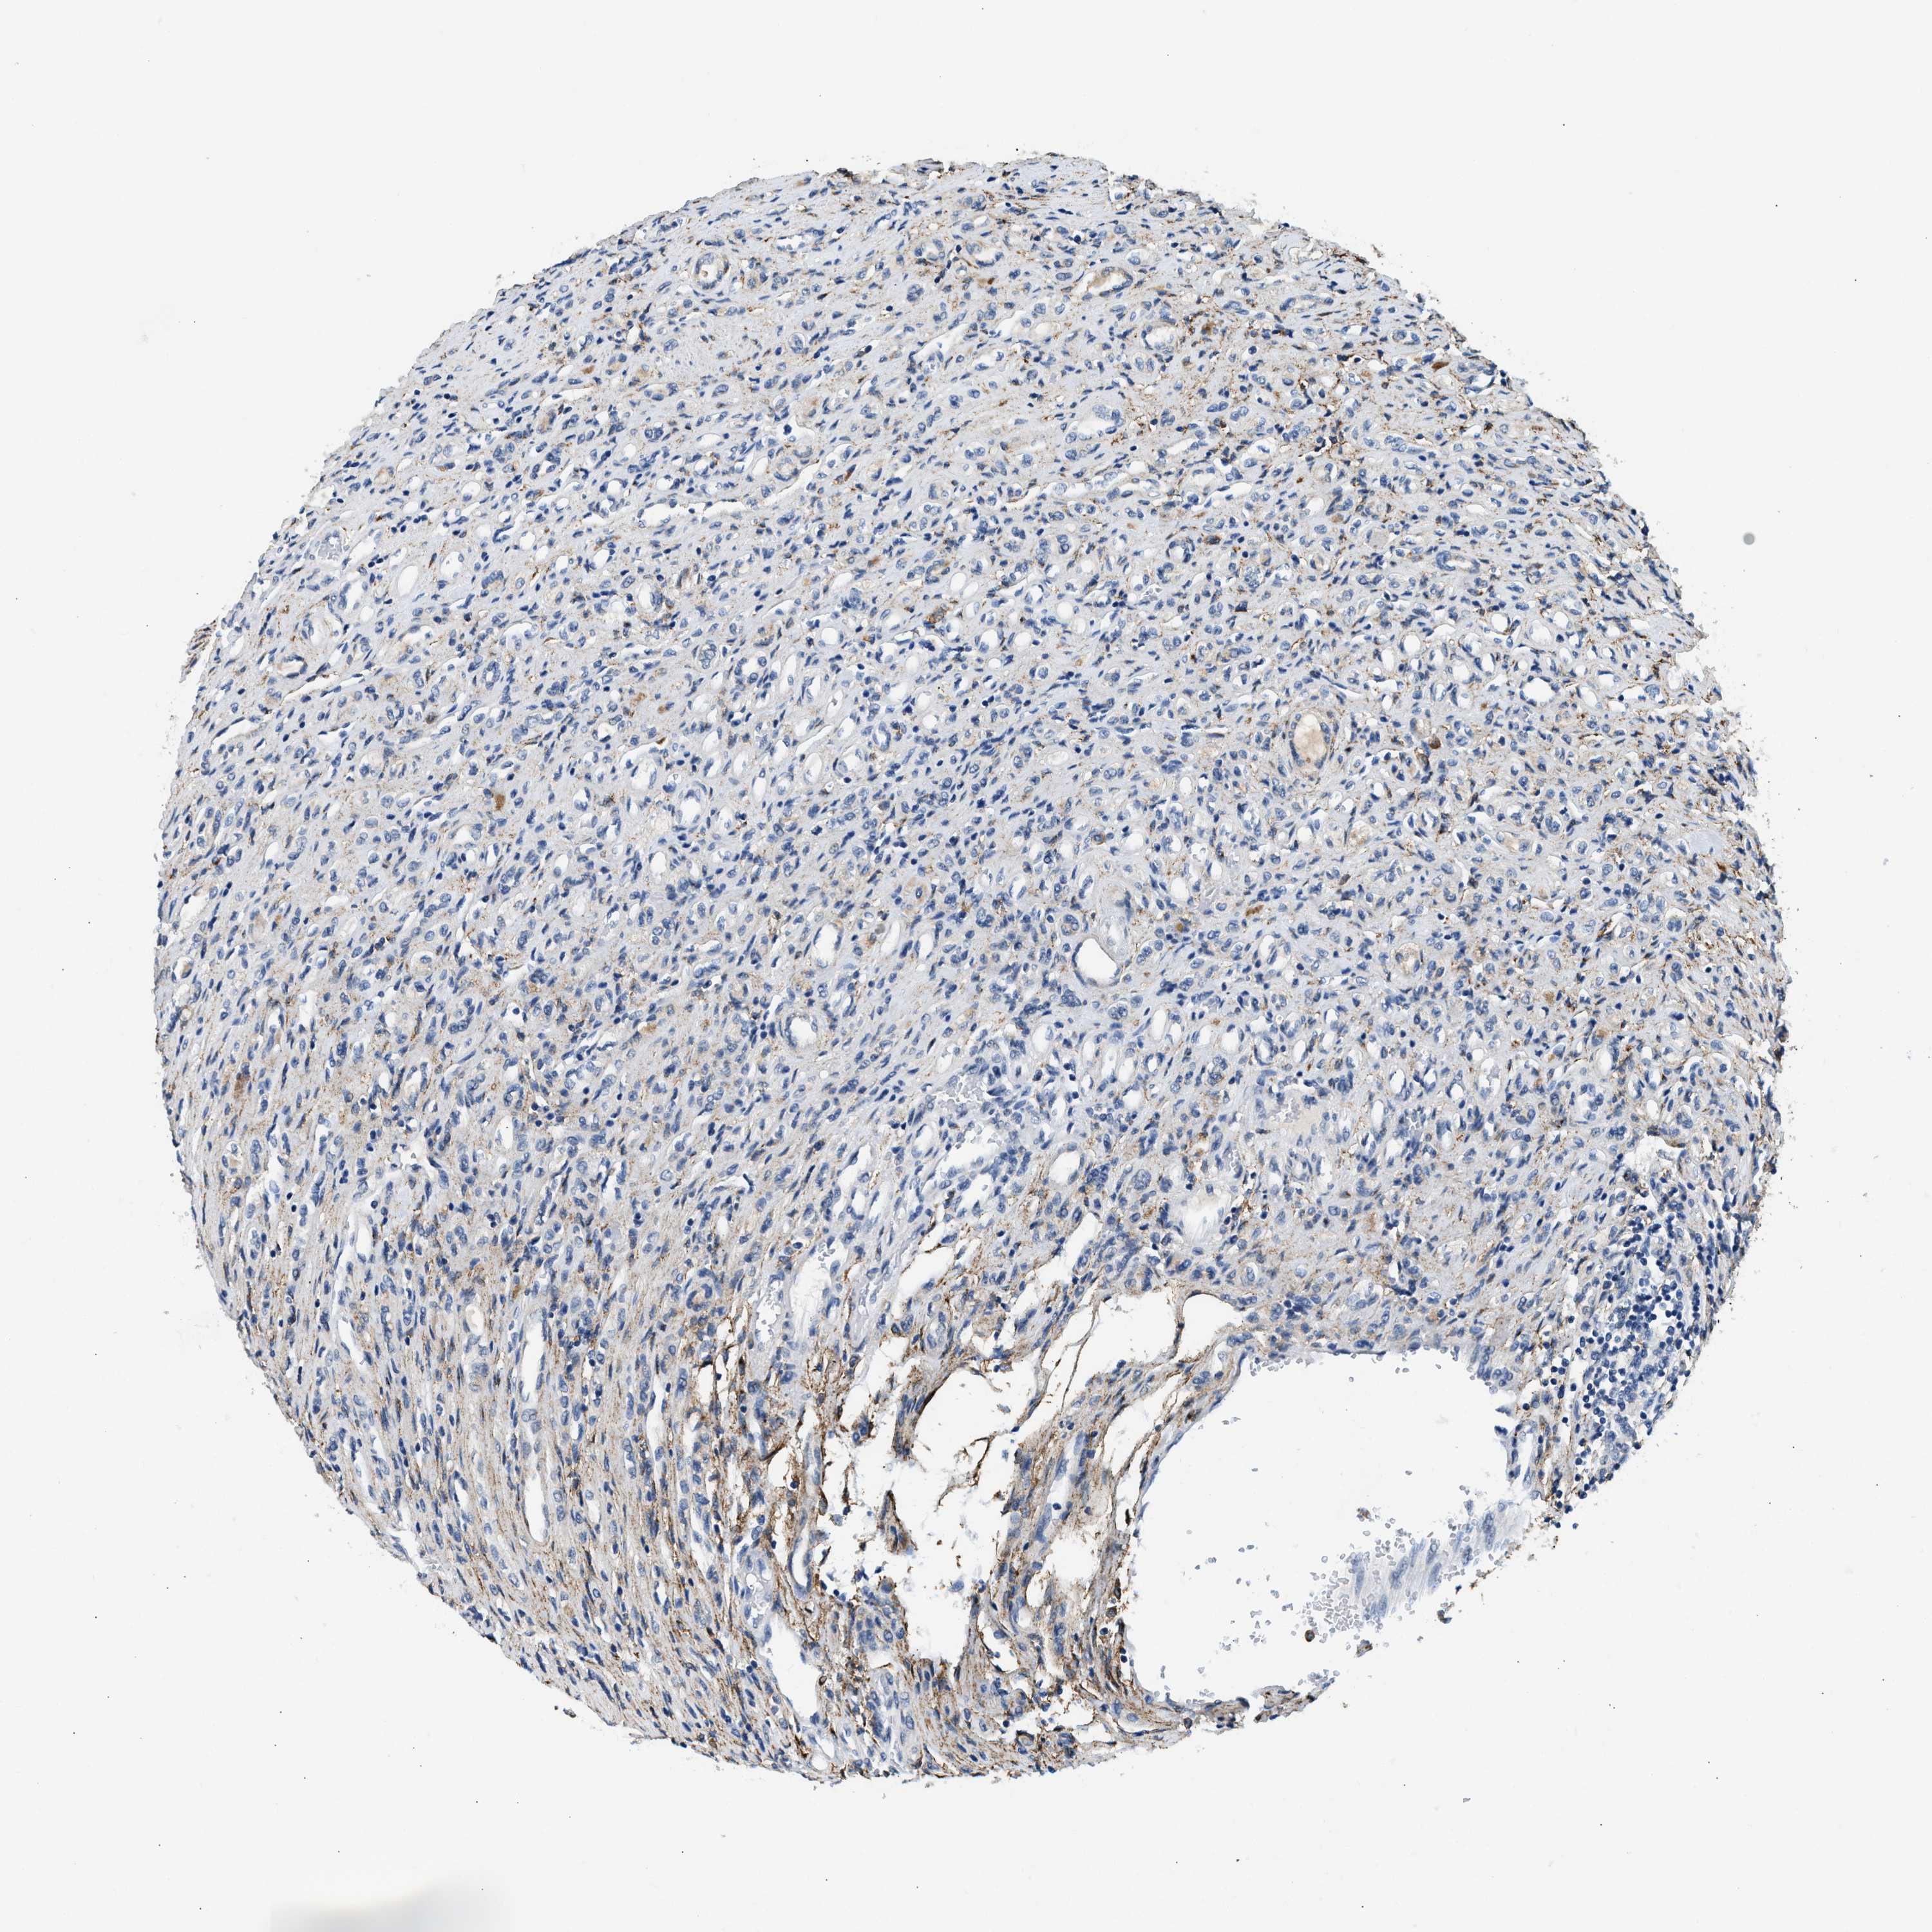

Renal cancer

Kidney renal papillary cell carcinoma

KIDNEY RENAL PAPILLARY CELL CARCINOMA (TCGA) - Interactive survival scatter ploti

LRP1 is not prognostic in Kidney Renal Papillary Cell Carcinoma (TCGA)